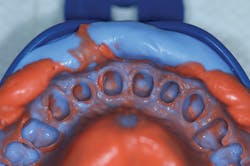

Once it was determined that the gingiva and soft tissue were healthy, a system of VPS impression materials was used to capture a final impression of the prepared teeth. A cordless impression technique was employed to accurately capture fine detail. In this technique, known as a hydraulic hydrophobic impression,2,3 a base VPS impression material was used (V-Posil Putty Fast, Voco) in order to capture the preliminary phase of the two-step impression (figure 5). Once completely set, the impression was removed, rinsed, and dried, and a light-body VPS impression material (V-Posil Light Fast, Voco) was injected into the entire intaglio of the base VPS (figure 6).

Figure 6: Injection of light-body VPS impression material